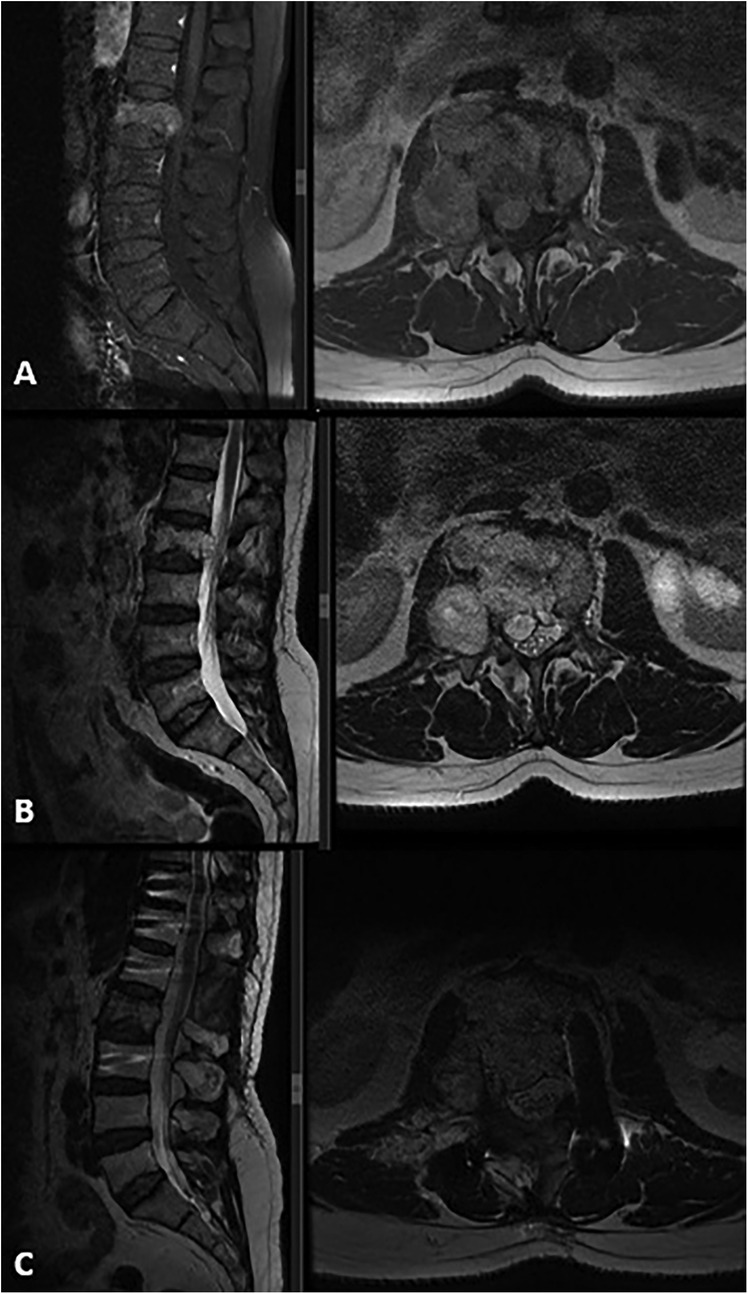

Three years after the initial operation, the patient presented with complaints of newly developed right-sided sciatica. Neurological examination at this time was unremarkable. A follow-up spinal MRI revealed the progression of the remnant tumor in the same region (Figures 3A,B). The patient underwent a second surgical procedure, during which the tumor was again removed subtotally (Figures 3C,D). As in the previous operation, the tumor was found to be purely extradural. This time, histopathological and immunohistochemical analysis of the specimen confirmed the diagnosis of chordoma. The tumor was predominantly composed of cells with clear or multivacuolated cytoplasm, occasionally forming chordoid and trabecular arrangements within a myxoid stroma. Immunohistochemically, the tumor cells were positive for cytokeratin (CK) AE1/AE3 and negative for S-100, RCC, CK14, CK7, CK20, and PAX8. The MIB-1 labeling index was 10%. Tumor cells showed diffuse positive staining for brachyury, a specific marker for tumors of notochordal origin. The postoperative course was again uneventful, the patients’ symptoms were relieved, and there were no neurological deficits after the surgery. Following the confirmed diagnosis of chordoma, proton beam therapy was administered with a total dose of 66 Gy delivered in 33 fractions. The spinal lesion remained stable over the next 3 years, during which the patient continued to be monitored regularly in the outpatient clinic.

MRI scans showing the lumbar spine in different sections: A and C depict sagittal views with a focus on the alignment and condition of vertebrae and intervertebral discs, highlighted by yellow lines. B and D present varying axial views, displaying the cross-section of the spine, emphasizing details of the spinal canal and surrounding tissues.

Figure 3. New spinal MRI performed 3 years after the initial surgery revealed a recurrent tumor with progression in the same region. It appeared hypointense on T1-weighted images (A) and hyperintense on T2-weighted sagittal and axial images (B), showing diffuse contrast enhancement, spinal canal extension, and dural sac compression. Postoperative T1-weighted (C) and T2-weighted (D) MRI images demonstrate subtotal tumor removal and adequate decompression.